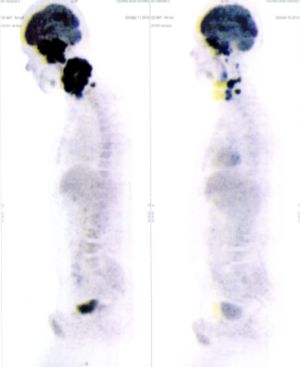

Below are some of the cases, from more than 80 cases we have treated so far with good results. When reading the PET/CT scans, the picture on the left is before treatment, and the picture on the right is after treatment. The intensity of black represents the activity of the cancer, but some black areas are not cancer: brain, heart, radioactive urine in bladder. For the heart, the intensity of black depends on the number of hours of fasting: if more than 10 hours, the heart is not even black, but if fasting is less than 6 hours, it is very black. The intensity of black in the brain can be variable in different scans depending on the brain activity at the time of the scan. The intensity of black in the radioactive urine can also be variable due to the hydration of patients and the time of injection of diuretic.

CASE NO: 3 (PROSTATE CANCER)

A middle-aged man with castration resistant prostate cancer, having failed all currently available cancer treatment, was very weak, and getting worse every day. The PET/CT scan showed he had massive bone metastases. After a few treatment, all the bone metastases went into remission. About 6 months later, he is still in remission.